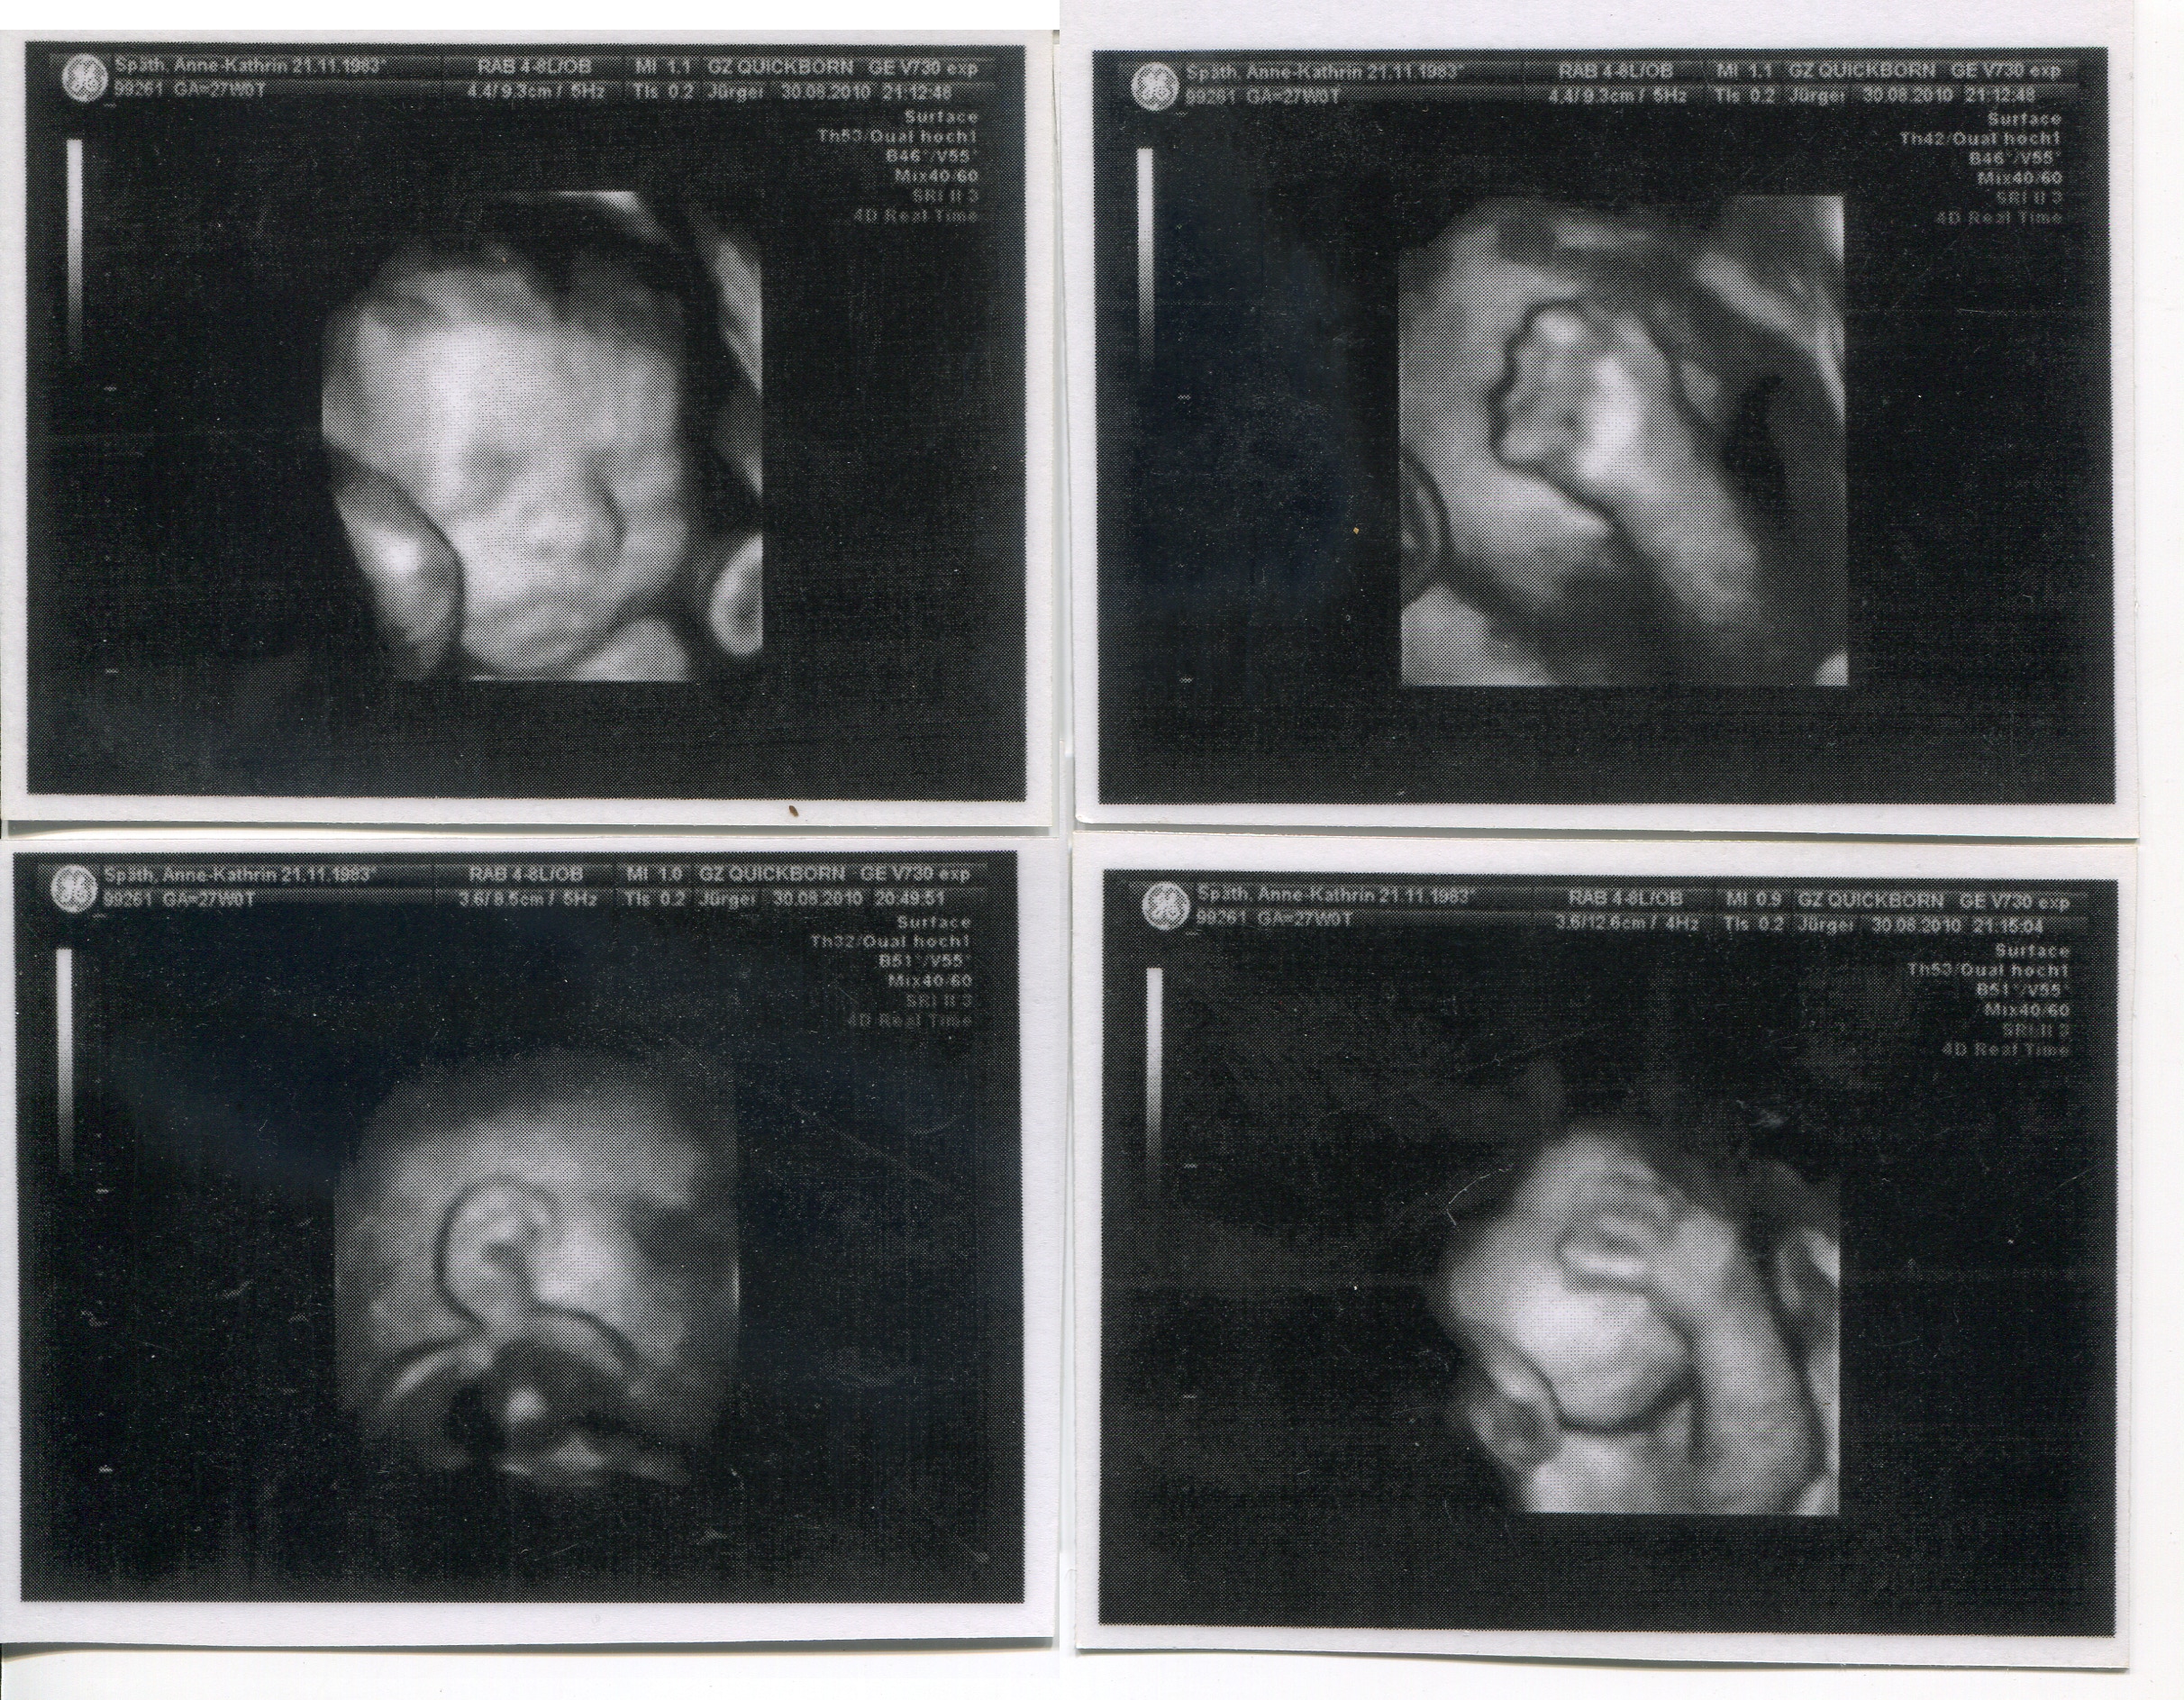

Klebealbum 1 Annes Geburt